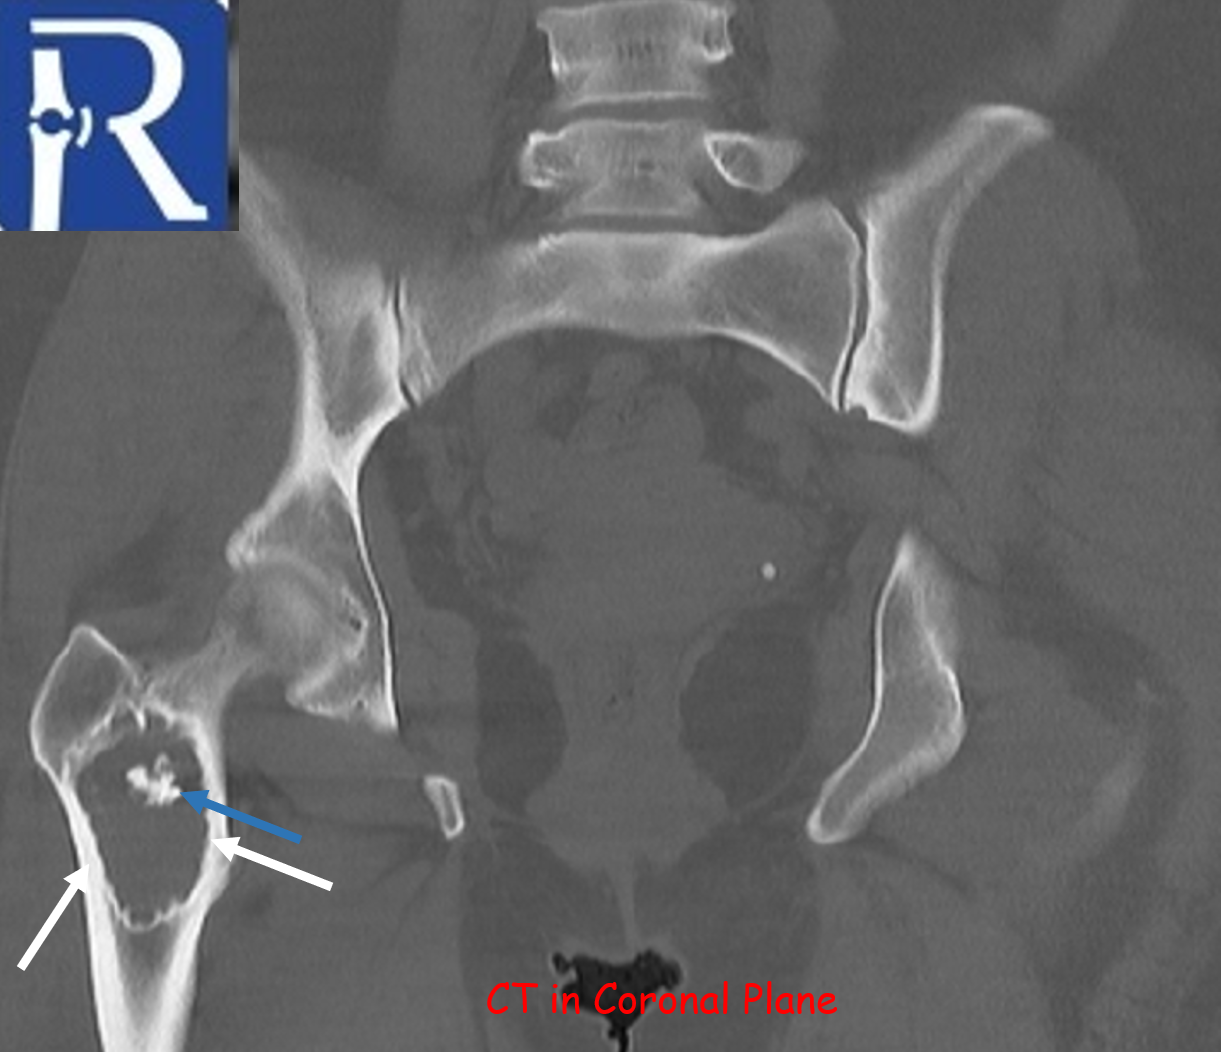

A geographic lytic lesion of Type I A pattern (white arrows) is observed on the right femur intertrochanteric-subtrochanteric area on the pelvic radiograph. The lesion is well-circumscribed and has a narrow transition zone. The internal content contains calcification (indicated by the blue arrow). Periosteal reaction is not visualised. The lesion demonstrates sclerotic areas corresponding to internal calcified foci. The lesion is compatible with liposclerosing myxofibrous tumors. In CT, the lesion matrix structures are more clearly visible, and the cortex appears intact. Calcification areas in the internal structure are more clearly observed. In MRI, the lesion appears as a low signal on the T1-weighted (T1W) sequence and as a high signal on the short tau inversion recovery (STIR) sequence, representing the myxoid content. Additionally, the calcification areas within the lesion exhibit low signals in both sequences.